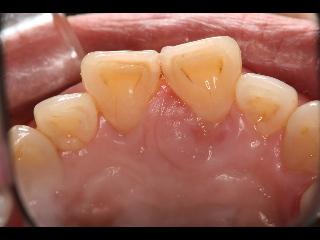

上の前歯の裏側です。右から3番目の歯ぐきが腫れています。

歯もぐらぐらしています。

腫れがなくなり、歯のぐらぐらもなくなりました。